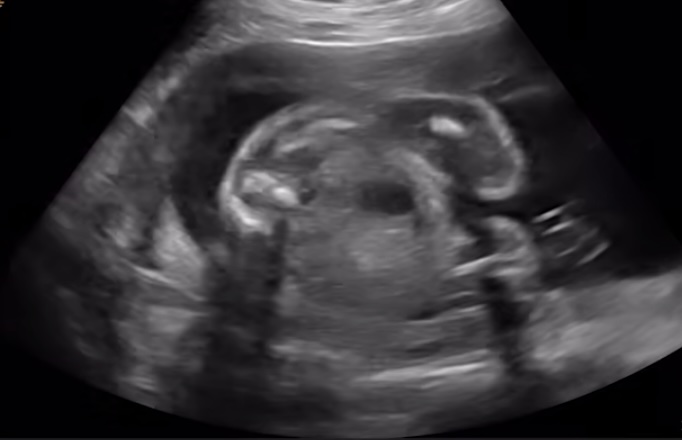

Kolposkopi:

- Anormal Pap smear veya pozitif yüksek riskli HPV testi sonucunda yapılan daha detaylı bir rahim ağzı incelemesidir.

- Kolposkop adı verilen özel bir mikroskop/büyüteç kullanılarak rahim ağzı, vajina ve vulva büyütülerek incelenir.

- İşlem sırasında rahim ağzına bazı özel solüsyonlar uygulanır:

- Asetik Asit (%3-5): Anormal hücrelerin bulunduğu alanların beyazlaşmasına (asetobeyaz epitel) neden olur. Bu alanlar biyopsi için potansiyel hedeflerdir.

- Lugol İyot Çözeltisi (Schiller Testi): Normal skuamöz epitel hücreleri glikojen içerdiği için iyotu tutarak kahverengiye boyanır. Anormal hücreler (CIN, kanser) veya glandüler hücreler glikojen içermediği için iyotu tutmaz ve sarı renkte kalır (iyot-negatif alanlar).

- Kolposkopi sırasında şüpheli görülen alanlardan biyopsi alınır.